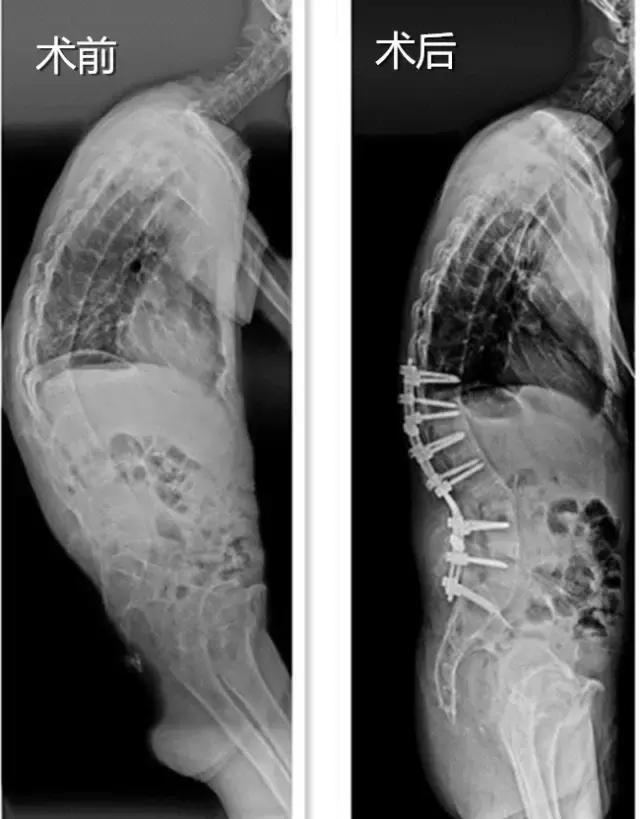

经过术前充分准备,李先生被送入手术室手术。医生在他弓起的脊柱部位切开了一个三十多厘米的口子,在脊柱的椎弓根上钉了两排各7颗的钛合金钉子,又在脊柱上截出一块倒三角形的骨头,合拢截面,弯曲的脊柱就被“拉直”了。

黄庆华主任说,这个手术最大的风险在于截骨的时候要避免伤及神经,否则患者有可能瘫痪,落下残疾。但是凭借市中心医院脊柱外科专家团队娴熟的手术技巧和密切合作,手术顺利完成,整个手术过程只用了3个多小时,术中出血仅600毫升左右。经过术后两个星期的康复治疗,李先生已经能佩戴支具下床行走,腰杆终于挺直了,走路再也不用“逢人哈腰”了。黄主任说,再过几个月,李先生基本上能正常生活了,对于一般的工作也能很好适应。